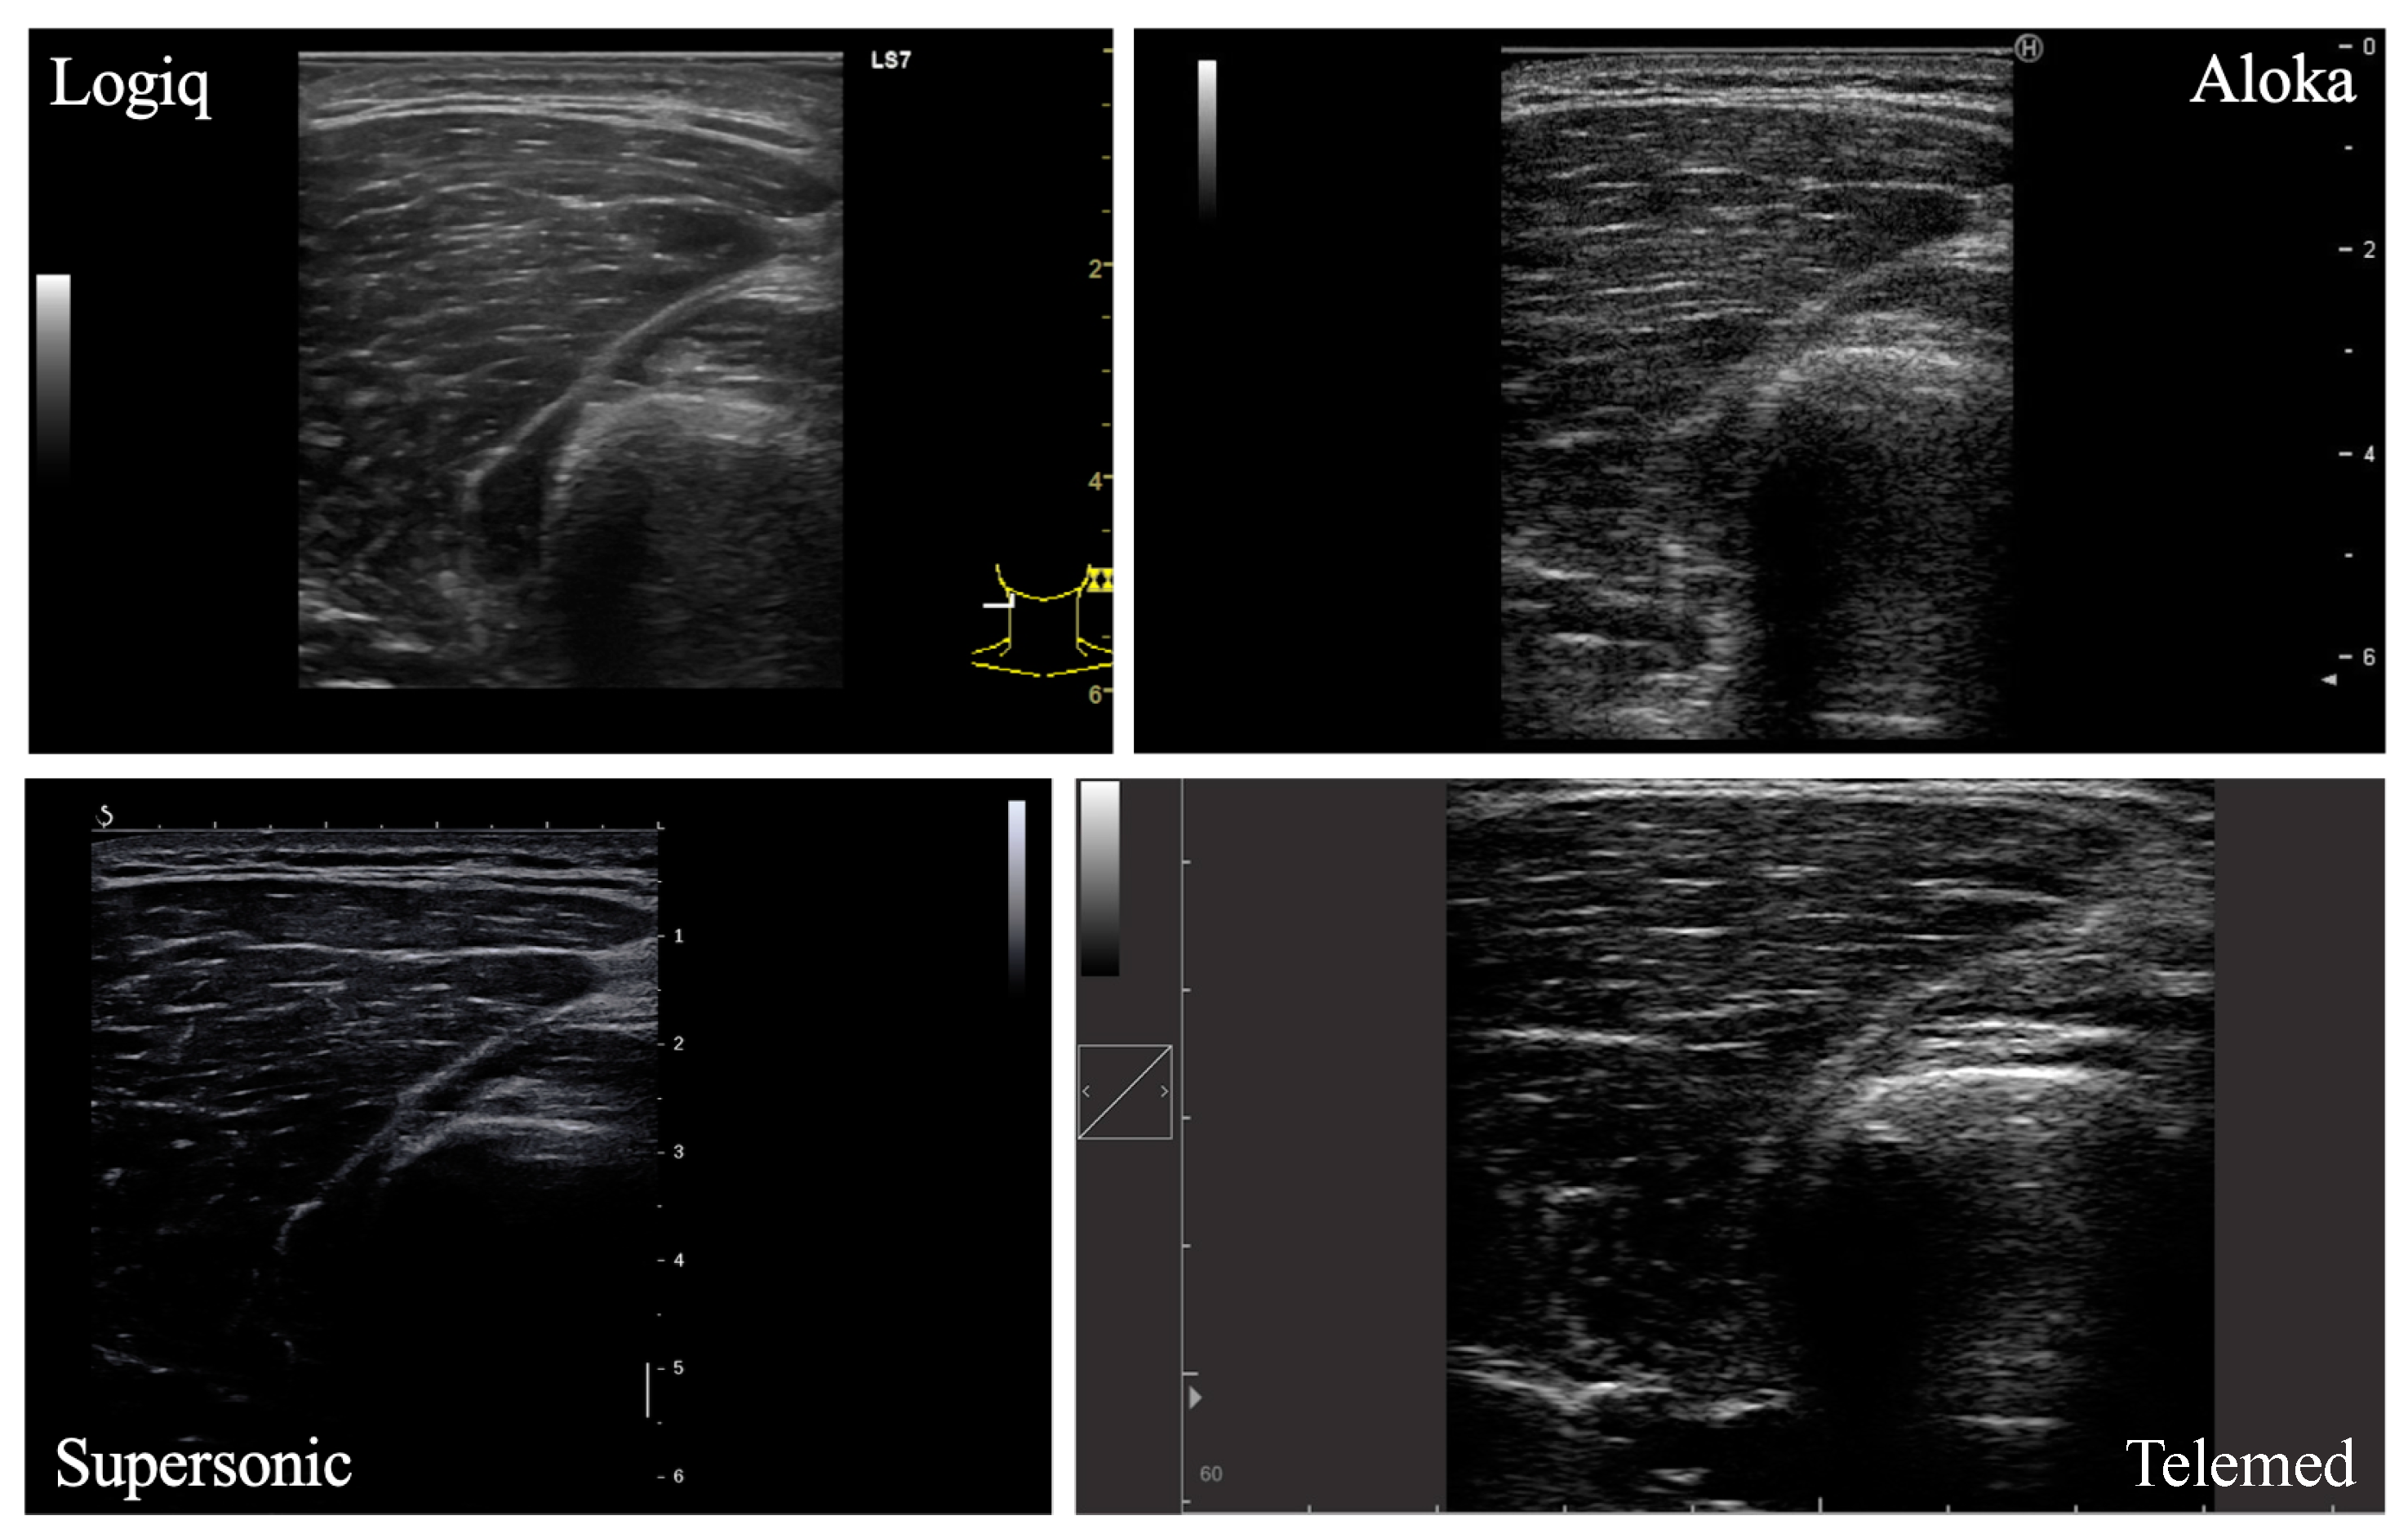

A total of four lower limb muscles were investigated in this study (VM, VL, GM, SOL; Figure 1). In each participant, the right leg was assessed by the same experimenter in a resting, supine position on an examination table. Four ultrasound devices, differing in terms of post-processing techniques and transducer characteristics, were used for analysis: LOGIQ (Logiq S7, GE Health Care, Chicago, IL, USA), SUPERSONIC (Aixplorer, Supersonic Imagine, Aix-en-Provence, France), ALOKA (Noblus, Hitachi–Aloka Medical Japan, Tokyo, Japan) and TELEMED (Echo Blaster 128 CEXT-1Z, Telemed Ltd., Vilnius, Lithuania) devices. Real-time brightness mode (B-mode) was used for all devices with specific parameters. Settings for each ultrasound device are reported in Table 1. The scanning depth was adjusted for participants with greater subcutaneous fat thickness to gather maximal muscle area. The other parameters were set in order to obtain a clear visualization of the muscle under consideration and its aponeuroses.

Figure 1. Ultrasound images of the vastus lateralis muscle from four different devices.